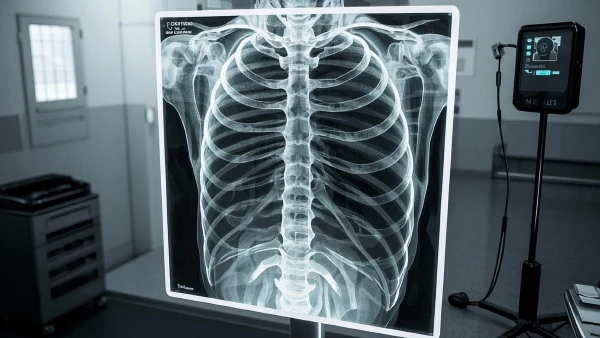

本文旨在全面介绍肋骨骨折的类型、诊断流程、分期标准、治疗方式、不良反应处理及患者生活习惯调整,帮助读者建立科学的疾病管理观念。 肋骨骨折是胸部外伤中最为常见的一种,通常由直接创伤造成,如交通事故、跌倒或运动损伤。肋骨骨折不仅可能引起剧烈疼痛,还可能带来一系列并发症,如呼吸困难和内脏损伤。虽然多数肋骨骨折可以通过保守治疗愈合,但严重的病例可能需要手术干预以确保患者的健康。 现代医疗技术的发展为肋骨骨折的诊断和治疗提供了更多细致和准确的手段。无论是影像学检查还是手术技术,都在不断进步,为患者争取更多的康复机会。除了医学技术的进步,综合的康复护理和病后生活调整同样是确保良好预后所必需的方面。

肋骨骨折可以根据多种标准进行分类,主要包括依据病因、病理生理和临床表现等几个方面。 根据病因,肋骨骨折可分为外伤性骨折和病理性骨折。外伤性骨折是最常见的类型,通常由直接或间接暴力引起,例如摔倒或车祸。病理性骨折则是由于骨骼本身的病变,如骨质疏松、肿瘤或感染,导致肋骨在轻微应力下骨折。 病理生理方面,肋骨骨折可以分为单纯性骨折和复杂性骨折。单纯性骨折仅涉及肋骨本身,并无明显的软组织或其它脏器损伤;复杂性骨折则伴有软组织损伤或内脏损害,如气胸、血胸等。 临床表现的分类可以根据受伤部位的不同分为前部、侧部和后部肋骨骨折。不同部位的骨折对患者的呼吸功能、疼痛感以及治疗方案有明显影响。例如,前部肋骨骨折更容易影响到胸廓的稳定性,而后部肋骨骨折则可能与脊柱损伤相关。 除了以上分类,还可能应用基于影像学结果的诊断分类。通过X光片、CT或者MRI等影像诊断手段,可以更精确地判断骨折的具体情况,从而为治疗提供依据。 总之,对肋骨骨折进行准确分类是制定有效治疗方案的前提,这需要综合考虑病因、病理生理特征和临床表现等多个因素。

肋骨骨折的诊断通常依赖于综合的临床评估和辅助检查,医生的丰富经验也是诊断过程的重要组成部分。 临床评估是肋骨骨折诊断的第一步。医生通常会通过病史采集、体格检查和症状描述来进行初步判断。患者常常报告剧烈的胸痛,尤其是在深呼吸、咳嗽或改变体位时疼痛加剧。触诊时,多数患者会在骨折处有明显的压痛点。 影像学检查是确认肋骨骨折的重要手段。X光拍片是最常见的基础检查,可以帮助识别明显的骨折及其碎片分布情况。对于一些复杂性骨折或怀疑有内脏损伤的病例,CT扫描则提供了更加详细的三维图像,有助于确认骨折的具体位置和程度。此外,MRI可以用于评估软组织和内脏器官的情况,如怀疑病理性骨折时尤为适用。 在实际的临床中,医生会综合影像学检查结果、病史和体格检查发现进行最终诊断。一些专业文献指出,综合检查的准确性高于单一检查方法。例如,《胸部外伤诊治指南》中强调,综合利用X光和CT检查有助于提高肋骨骨折诊断的准确性。 在肋骨骨折的诊断过程中,医生还应关注并发症的存在,例如气胸、血胸或者肺挫伤等。通过胸部听诊、脉搏血氧仪和其他辅助检查手段,可以进一步评估患者的呼吸功能和生命体征,确保及时发现并处理潜在的危险情况。 综上所述,肋骨骨折的诊断需要依靠多种检查手段的综合应用,医生应积累丰富的临床经验,以提高诊断的准确性和及时性,确保为患者提供最佳的治疗方案。